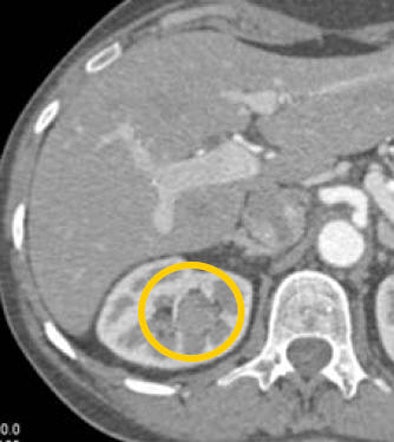

CT images from a patient with transitional cell carcinoma (TCC) were also best appreciated in late-phase imaging. The early-phase data showed slight differential diffusion between the right and left kidneys and a subtle lower-density region in the right kidney. With excretory-phase imaging, the TCC was visible in the axial view and was even more clearly defined in the coronal view.

![]() |

| In a patient with TCC, slight perfusion differences can be seen between the right and left kidneys in the arterial phase (above), and a subtle lower-density zone can be appreciated in the right kidney. On excretory-phase imaging, in both the axial view (below) and coronal view (bottom) it becomes an obvious infiltrative tumor. |